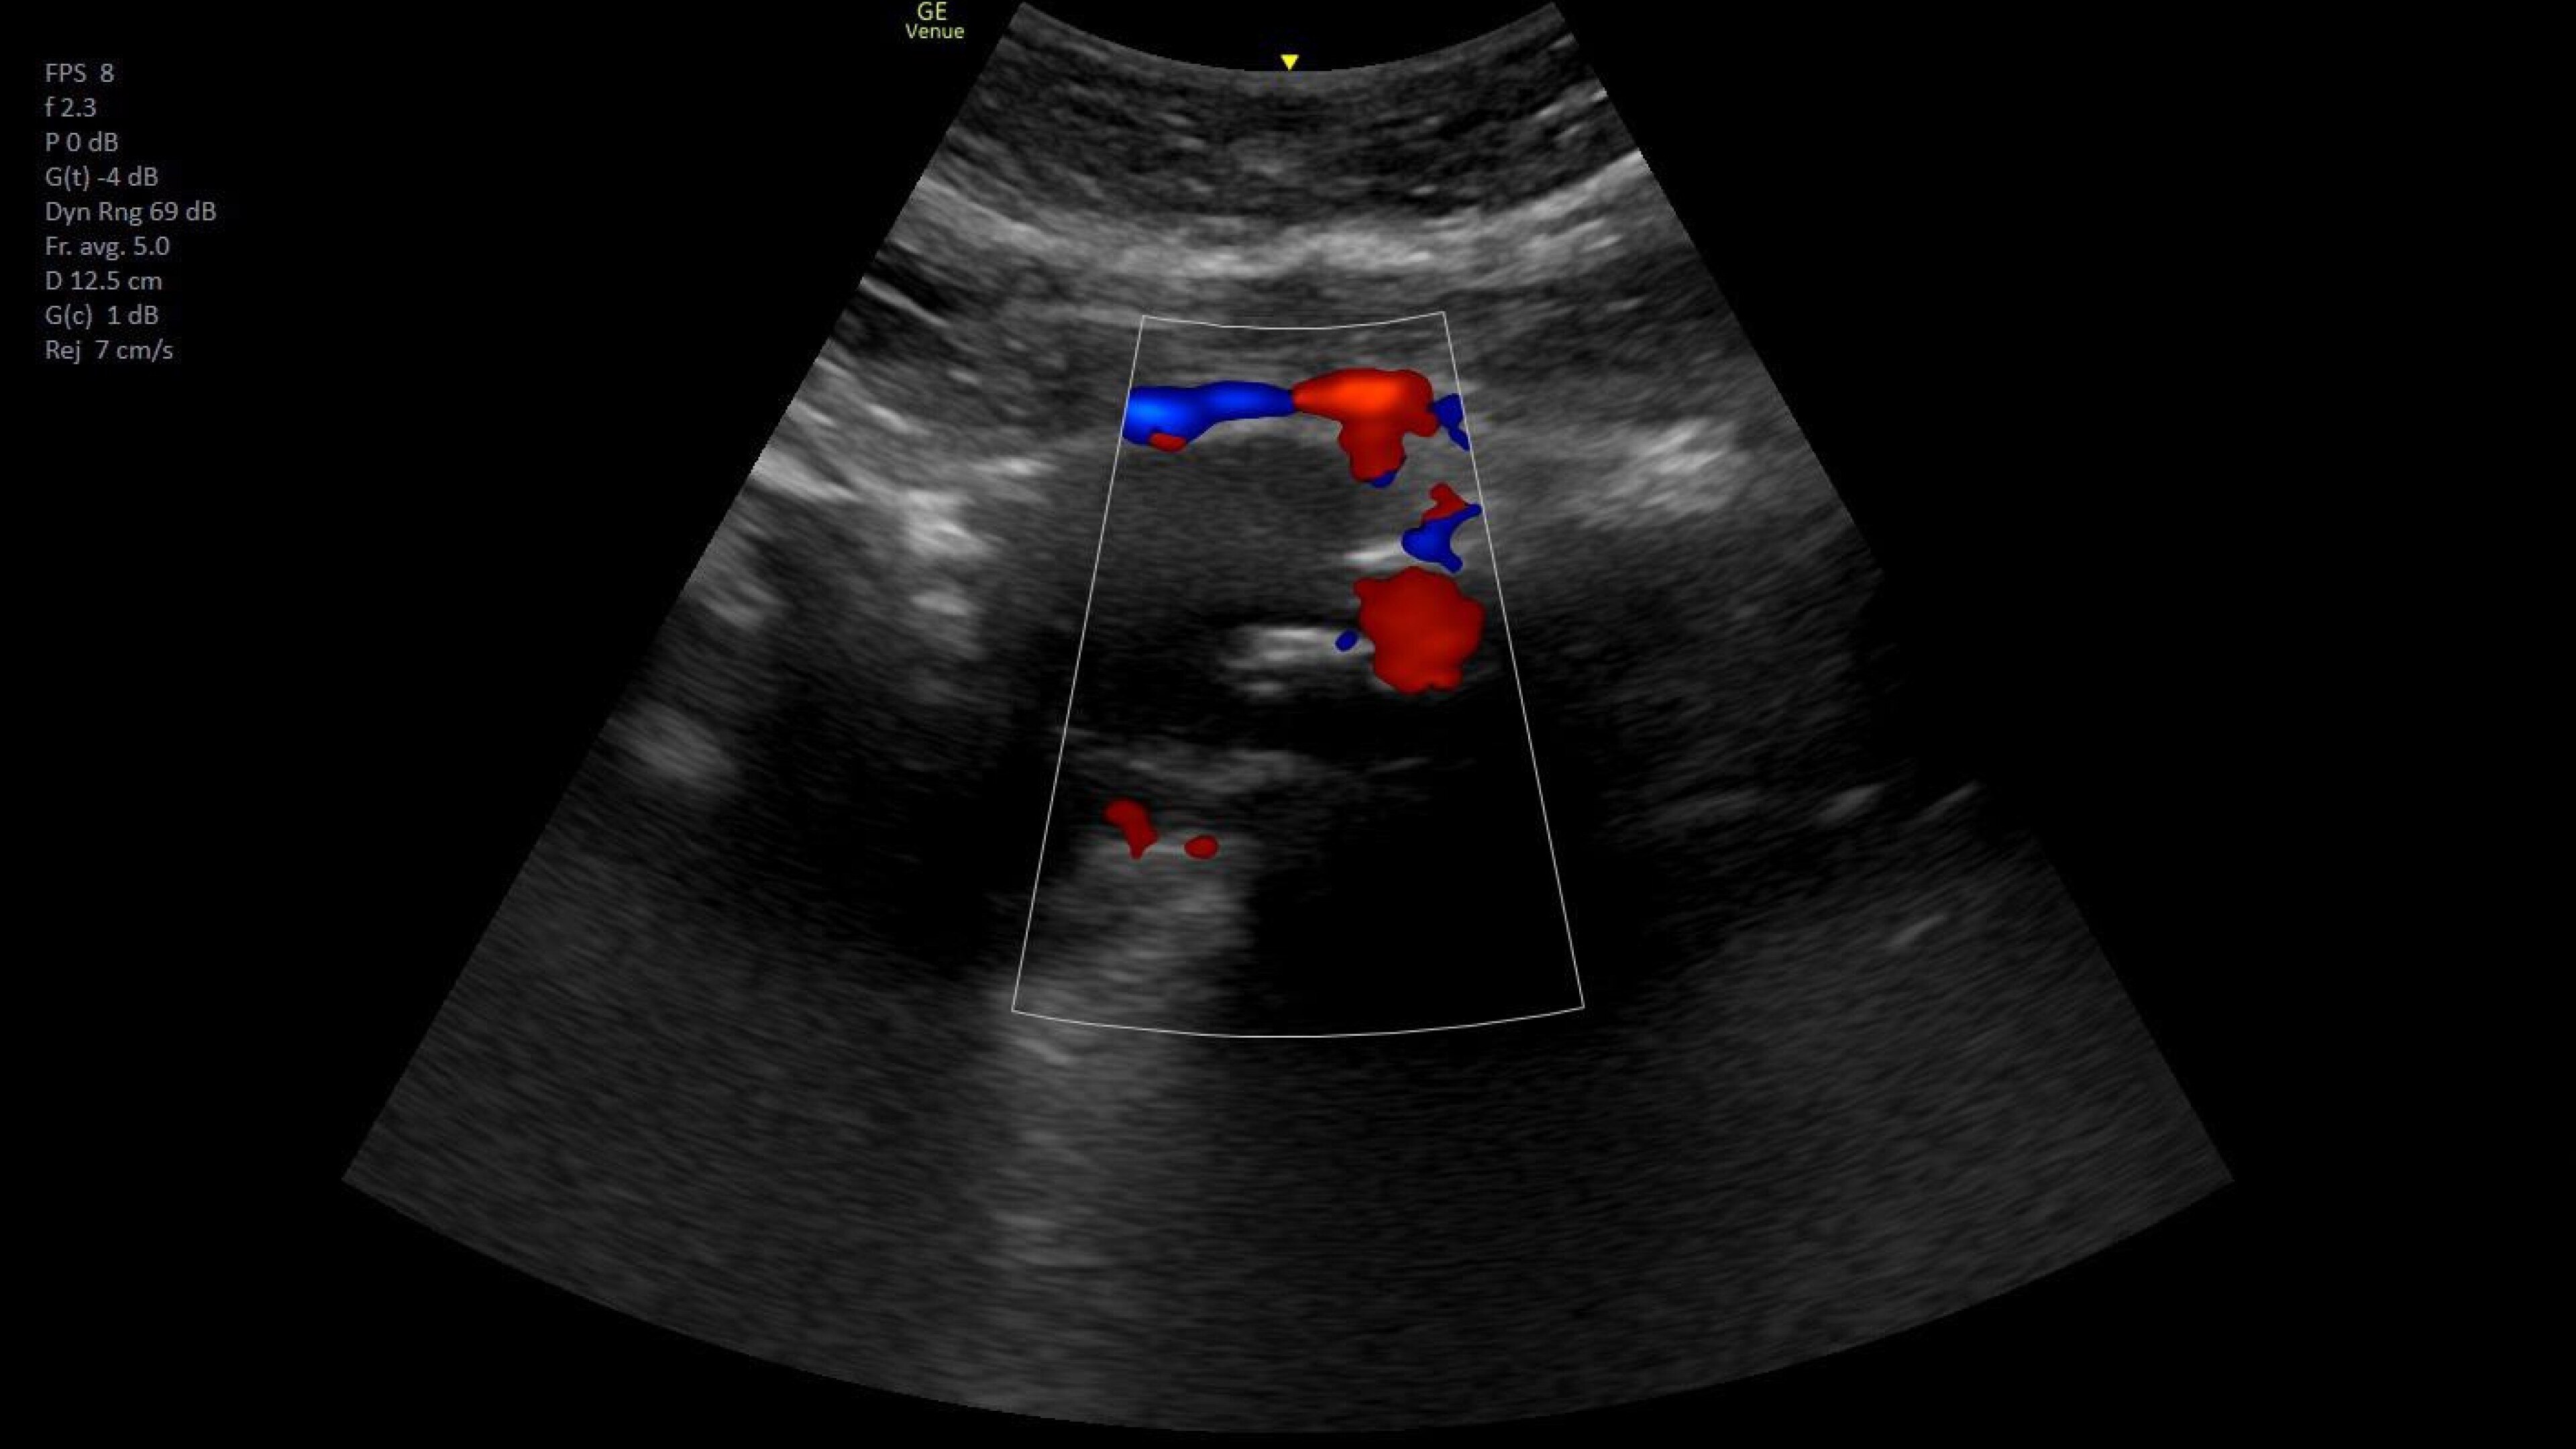

Vascular access

Helps you to assess vascular diseases, from cardiovascular conditions and peripheral vascular disease to pulmonary vascular disease.

Great for superficial Color flow imaging, chin and jawline anatomy and other ultrasound scans used in aesthetic procedures.

06-aesthetics